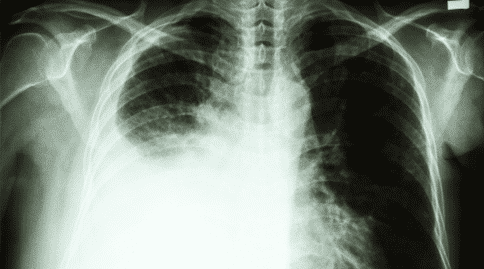

近年來(lái),肺癌的發(fā)病率直線上升,我國(guó)已成為肺癌發(fā)病率較高的國(guó)家之一,如果早期發(fā)現(xiàn)肺癌,提高肺癌五年內(nèi)生存率成為了目前人們面臨的一個(gè)重大難關(guān)。

根據(jù)IASLC 2019年世界大會(huì)上提出的研究報(bào)告,結(jié)合早期自身抗體檢測(cè)以及CT成像,可以減少肺癌晚期診斷,并可能降低肺癌特異性死亡率。這項(xiàng)研究是由英國(guó)圣安德魯斯大學(xué)的弗蘭克·沙利文教授提出的。

沙利文和他的團(tuán)隊(duì)試圖使用EarlyCDT?-Lung Test進(jìn)行檢查,然后進(jìn)行X線和CT掃描,研究其是否可以識(shí)別肺癌高風(fēng)險(xiǎn)患者,并降低晚期肺癌或非分類患者的發(fā)病率( U)。